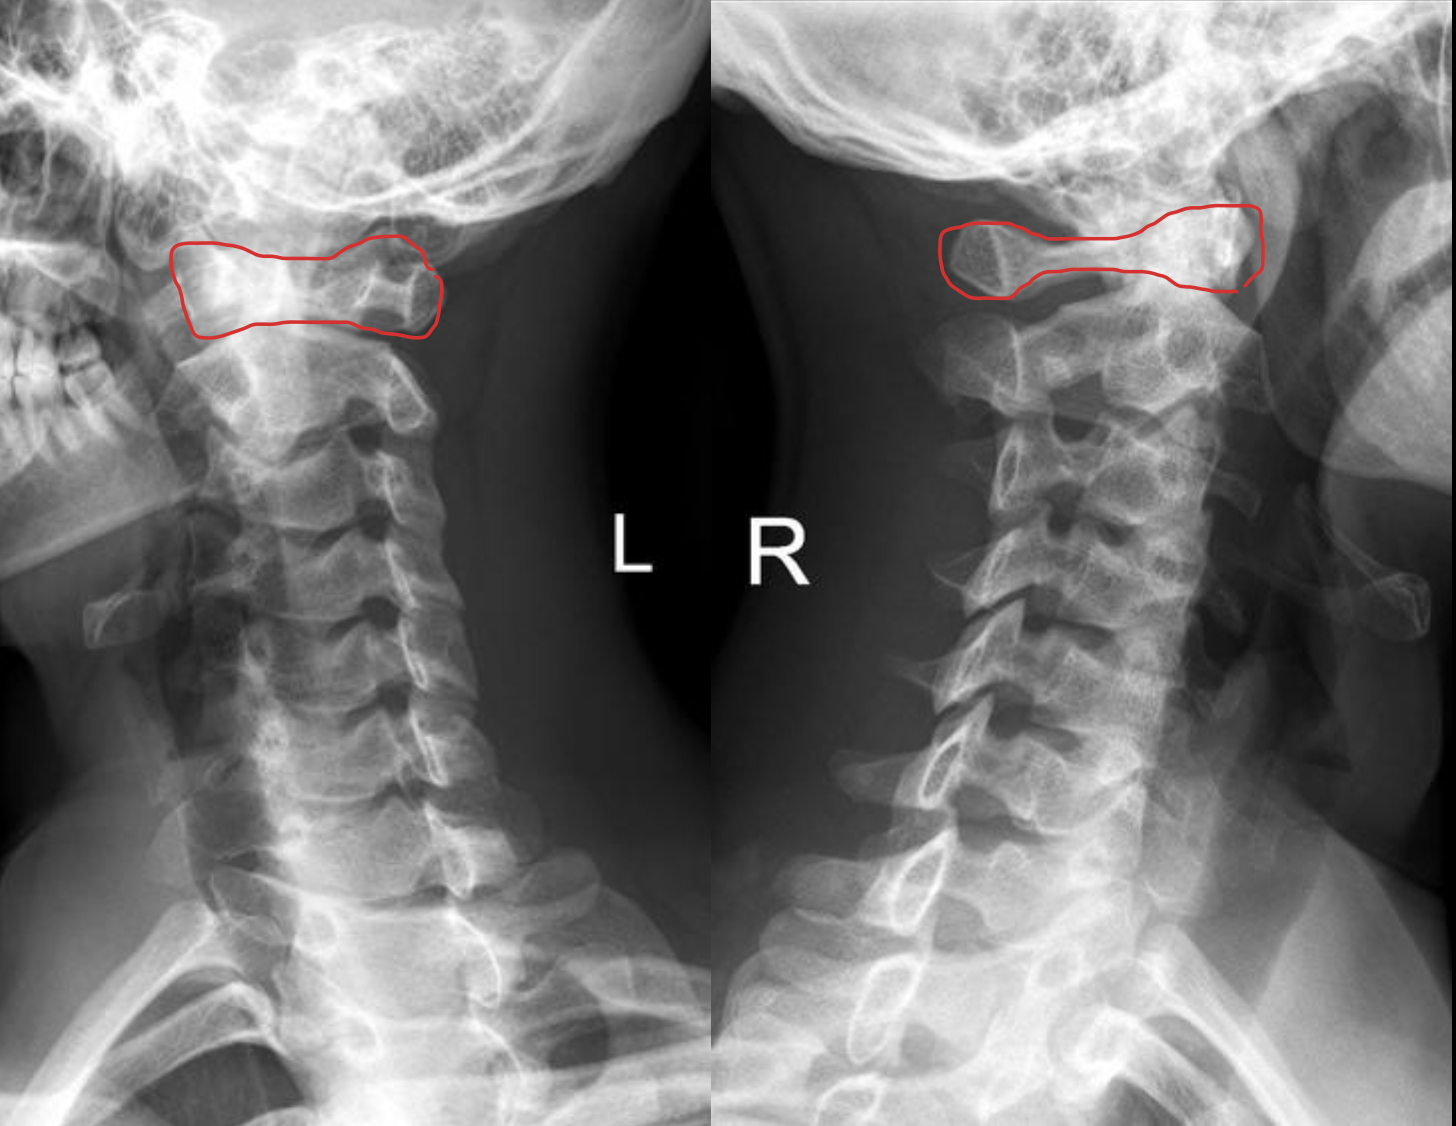

寰椎前结节

C1 anterior tubercle

寰椎后弓及后结节

C1 posterior arch & tubercle

关节突

Articular process

椎间孔

Intervertebral Foramina

椎弓根

Pedicle

T1

椎间盘

Intervertebral disc

关节突关节(小关节)

Zygapophyseal

齿状突(枢椎齿突)

Odontoid

Posterior arch & Tubercle of C1

棘突

Spinous process

椎间盘(Intervertebral Disc)

IVD

寰椎前弓

Anterior arch of C1